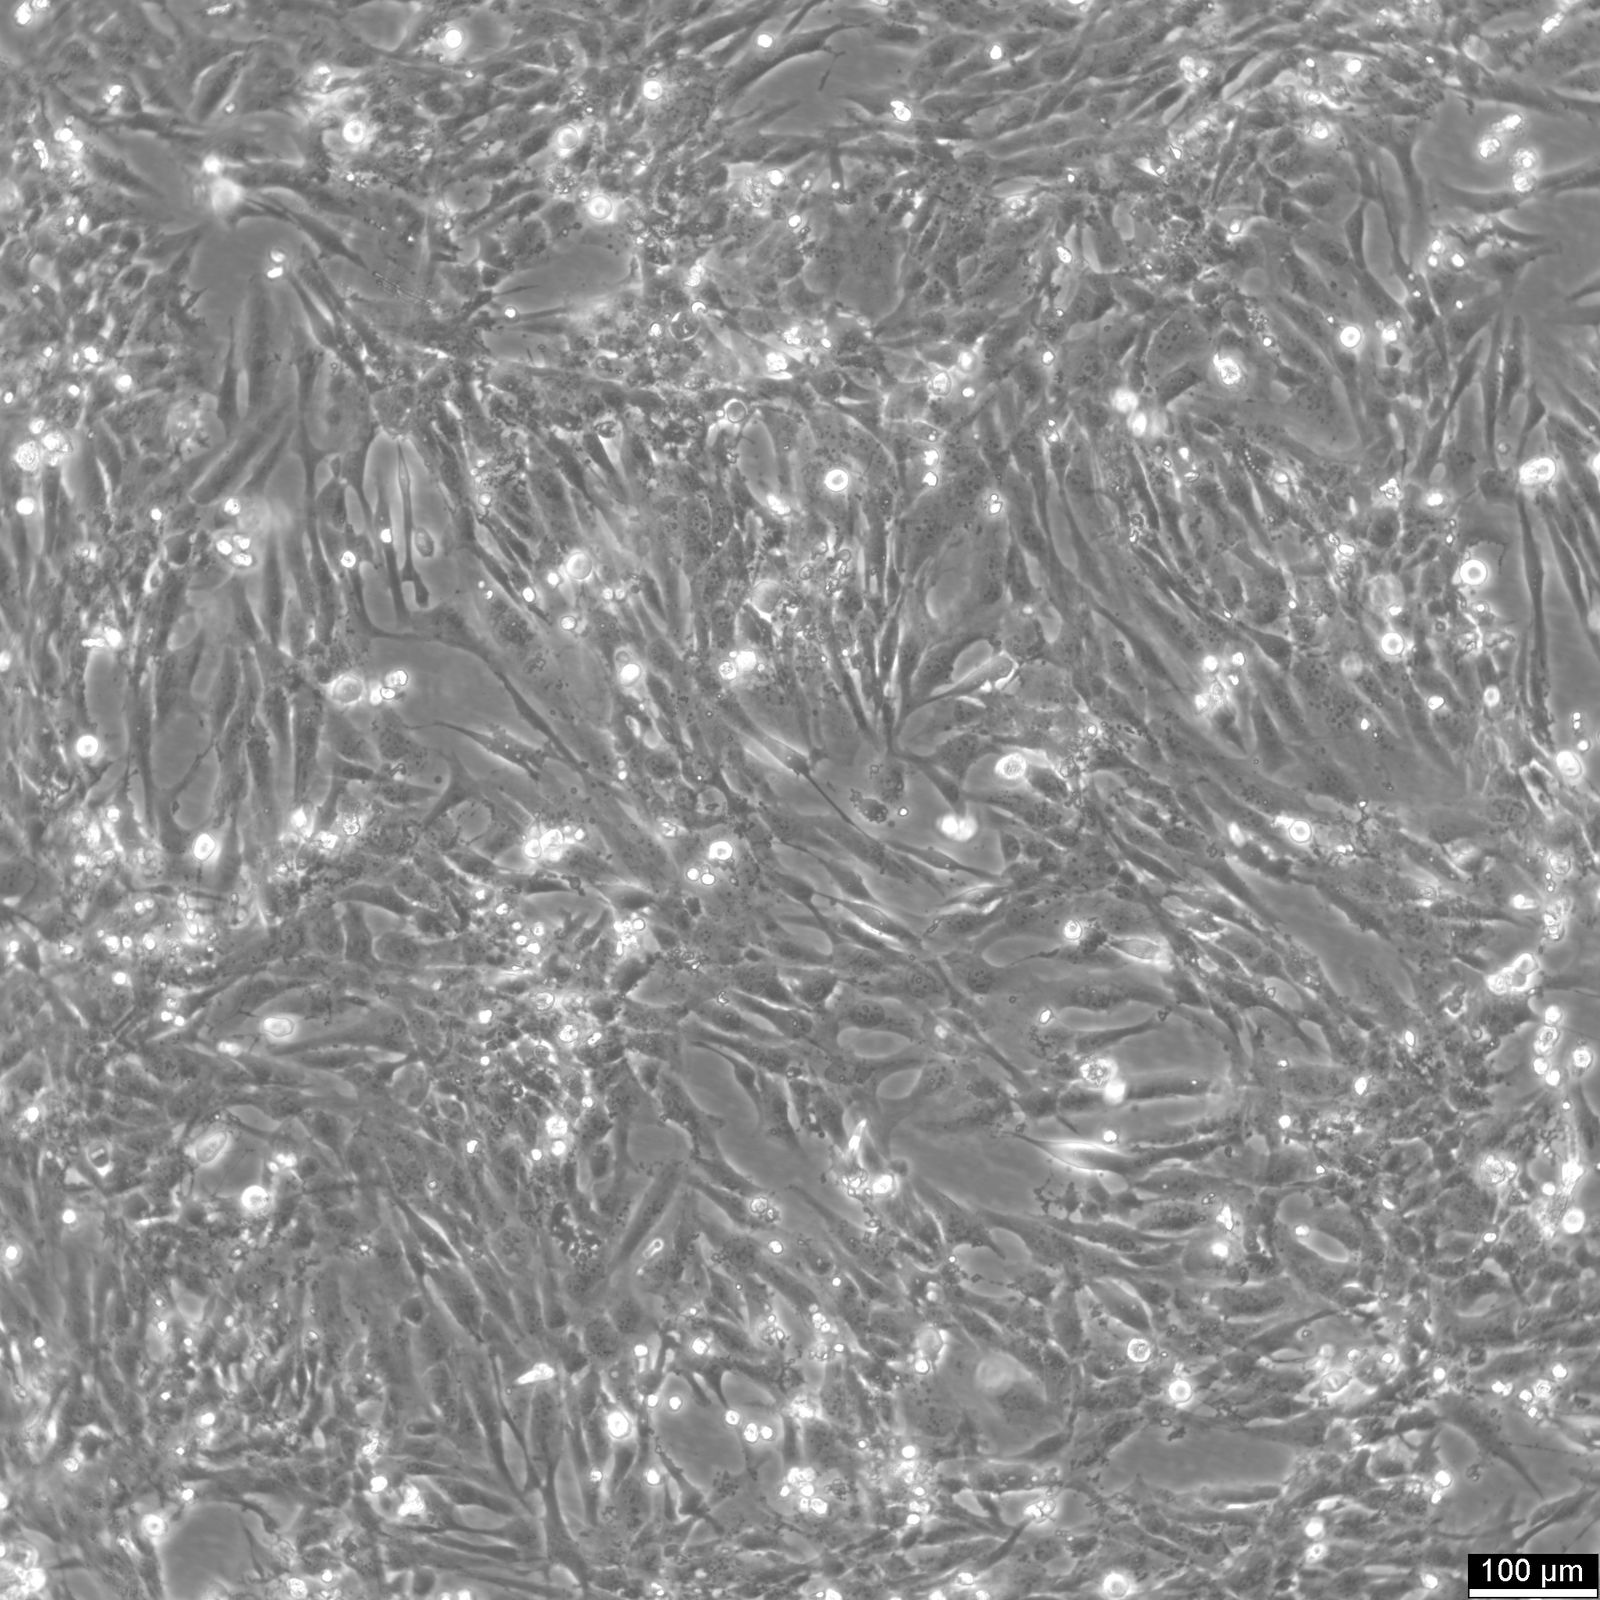

Categories: Hybrid cell lines Description: The AC16 cell line, derived from human ventricular cells fused with SV40-transformed, showcases characteristics typical of cardiomyocytes, including the expression of transcription factors such as GATA4, MYCD, NFATc4, and contractile proteins like alpha- and beta-myosin heavy chain. AC16 cells also express gap junction proteins connexin-43 and connexin-40, with functional gap junctions confirmed by dye-coupling studies, underscoring their utility in cardiomyocyte research. When the SV40 oncogene is silenced, AC16 transitions towards a more differentiated state, marked by the expression of BMP2, indicative of cardiac differentiation and developmental regulation. In general, scientists employ various techniques, including stem cell differentiation, animal models, molecular analysis, and biomarker discovery, to advance knowledge and potential therapies for heart-related conditions. The involvement of mitogen and senescence pathways, along with thymidine kinase induction, further elucidates the complex nature of human cardiomyocytes and their response to pathological conditions. The AC16 human cardiomyocyte cell line's ability to mimic the behavior of mature cardiomyocytes makes it a valuable model for cardiac research. It closely resembles the genetic makeup of primary cardiomyocytes, allowing for studies on cardiac development, pathology, and the implications of histone loss in vitro, however, the cardiomyocyte behavior and genetic complexity might not fully match that of primary or stem cell-derived cardiomyocytes. In the context of toxicology and cardiovascular disease research, AC16 cells serve as a vital tool for understanding cardiomyocyte development, inflammation, injury, regeneration, and toxicological effects. The unique properties of the AC16 human cardiomyocyte cell line, including its response to developmental cues and the ability to simulate the physiological conditions of human cardiomyocytes, make it an indispensable asset in the quest to unravel the mysteries of heart diseases and devise novel therapeutic interventions. Organism: Human Tissue: Heart, ventricle Synonyms: Human hybrid cardiomyocyte Ethnicity: Caucasian Morphology: Epithelial Cell Type: Cardiomyocyte Growth Properties: Adherent Citation: AC16 Cardiomyocyte Cell Line (Cytion catalog number 305215) Biosafety Level: 1 Ncbi_ Taxid: 9606.0 Cellosaurus Accession: CVCL_4U18 Viruses: Transformed by the SV40 large T-antigen Culture Medium: Culture medium:DMEM:Ham's F12 (1:1), w: 3.1 g/L Glucose, w: 2.5 mM L-Glutamine, w: 15 mM HEPES, w: 0.5 mM Sodium pyruvate, w: 1.2 g/L NaHCO3 (Cytion article number 820400a). Supplement the culture medium with 12.5% FBS and add 0.9 mM L-Glutamine to achieve a final concentration of 2.5 mM L-Glutamine. Differentiation medium: DMEM:Ham's F12 (1:1), w: 3.1 g/L Glucose, w: 2.5 mM L-Glutamine, w: 15 mM HEPES, w: 0.5 mM Sodium pyruvate, w: 1.2 g/L NaHCO3 (Cytion article number 820400a). To prepare the complete differentiation medium, add 1x ITS+ (Gibco, catalog number 41400045) and 2% Horse Serum (Gibco, catalog number 16050130). Dissociation Reagent: Accutase Subculturing: Remove the old medium from the adherent cells and wash them with PBS that lacks calcium and magnesium. For T25 flasks, use 3-5 ml of PBS, and for T75 flasks, use 5-10 ml. Then, cover the cells completely with Accutase, using 1-2 ml for T25 flasks and 2.5 ml for T75 flasks. Let the cells incubate at room temperature for 8-10 minutes to detach them. After incubation, gently mix the cells with 10 ml of medium to resuspend them, then centrifuge at 300xg for 3 minutes. Discard the supernatant, resuspend the cells in fresh medium, and transfer them into new flasks that already contain fresh medium. Freeze Medium: As a cryopreservation medium, use complete growth medium (including FBS) + 10% DMSO for adequate post-thaw viability, or CM-1 (Cytion catalog number 800100), which includes optimized osmoprotectants and metabolic stabilizers to enhance recovery and reduce cryo-induced stress. Thawing And Culturing Cells: Confirm that the vial remains deeply frozen upon delivery, as cells are shipped on dry ice to maintain optimal temperatures during transit. Upon receipt, either store the cryovial immediately at temperatures below -150°C to ensure the preservation of cellular integrity, or proceed to step 3 if immediate culturing is required. For immediate culturing, swiftly thaw the vial by immersing it in a 37°C water bath with clean water and an antimicrobial agent, agitating gently for 40-60 seconds until a small ice clump remains. Perform all subsequent steps under sterile conditions in a flow hood, disinfecting the cryovial with 70% ethanol before opening. Carefully open the disinfected vial and transfer the cell suspension into a 15 ml centrifuge tube containing 8 ml of room-temperature culture medium, mixing gently. Centrifuge the mixture at 300 x g for 3 minutes to separate the cells and carefully discard the supernatant containing residual freezing medium. Gently resuspend the cell pellet in 10 ml of fresh culture medium. For adherent cells, divide the suspension between two T25 culture flasks, for suspension cultures, transfer all the medium into one T25 flask to promote effective cell interaction and growth. Adhere to established subculture protocols for continued growth and maintenance of the cell line, ensuring reliable experimental outcomes. Sterility: Mycoplasma contamination is excluded using both PCR-based assays and luminescence-based mycoplasma detection methods. To ensure there is no bacterial, fungal, or yeast contamination, cell cultures are subjected to daily visual inspections. Safety Precautions: When planning to store a cryovial in liquid nitrogen for future thawing, it is mandatory to adhere to stringent safety measures. Appropriate protective gloves and clothing are essential, and the use of a face mask or safety goggles is required during the transfer of frozen samples to or from the liquid nitrogen tank. This is to mitigate the risk of injury from potential cryovial explosions upon removal, which can result in the projection of sharp fragments. Warranty: We stand by the promise of delivering products with high cell viability and robust culture performance. To achieve the best results, please make sure you follow the storage and culture instructions detailed in the product information sheet closely. Your adherence to these guidelines is key to success. Subject To Material Transfer Agreements: If you intend to use Cytion cell lines solely for internal research at a single research site, please complete and sign our Material Transfer Agreement (MTA) and submit it along with your order.For any commercial applications - including but not limited to fee-for-service work, quality control testing, product release, diagnostic use, or regulatory studies - please complete the Intended Use Form so we can prepare a suitable agreement tailored to your project.Please note: The MTA applies only to certain cell lines. If this notice and the MTA document appear on a product page, the agreement is applicable. For cell lines not covered by the MTA, no reference to the agreement will be shown. The MTA is not valid for customers in the Americas, China, or Taiwan. Please contact our U.S. entity to receive the appropriate agreement. Required Product 1: 820400a Required Product 3: 860015.0 Required Product 4: 830100.0